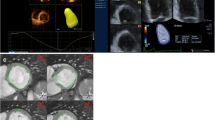

For quantification of the HAND and SE dataset the Auto Strain (AS) tool (TOMTEC—ARENA Lot 50, TOMTEC Imaging Systems GmbH, Germany) was used. This tool automatically identifies the end-diastolic and end-systolic frames using the ECG signal.

However, as the HAND dataset did not contain an ECG signal, the end-diastolic and end-systolic frames had to be selected manually using M-mode tracing through the mitral valve annulus. Next, based on the automatically traced LV blood-tissue boundaries (Figs. 1 and 2) and the Simpson’s biplane method, SV and LVEF were calculated.

For 3DE quantification the Dynamic HeartModelA.I. (DHM, Philips Ultrasound, Inc., Bothell, WA) was used. This tool automatically identifies the end-diastolic and end-systolic frames from the cardiac cycle using ECG and creates end-diastolic and end-systolic 3D projections of the LV cavity. From these 3D projections LV parameters were derived directly. Manual adjustments to the endocardial border tracings were not supported by DHM. Hence, when the operator judged the automatically detected endocardial borders to be incorrect, those images were excluded from analysis.